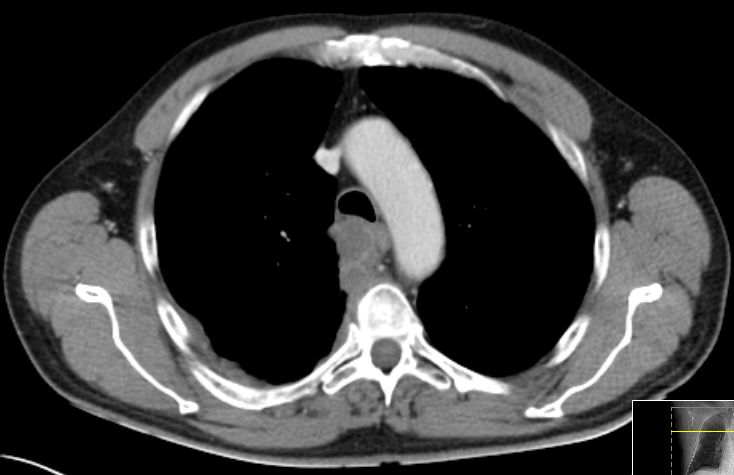

Primär zerebral metastasiertes Adenokarzinom des rechten Unterlappens. Im CT Tumor kavernenartig zerfallend. Jetzt: Sero-Pneu.

Sero-Pneu im CT